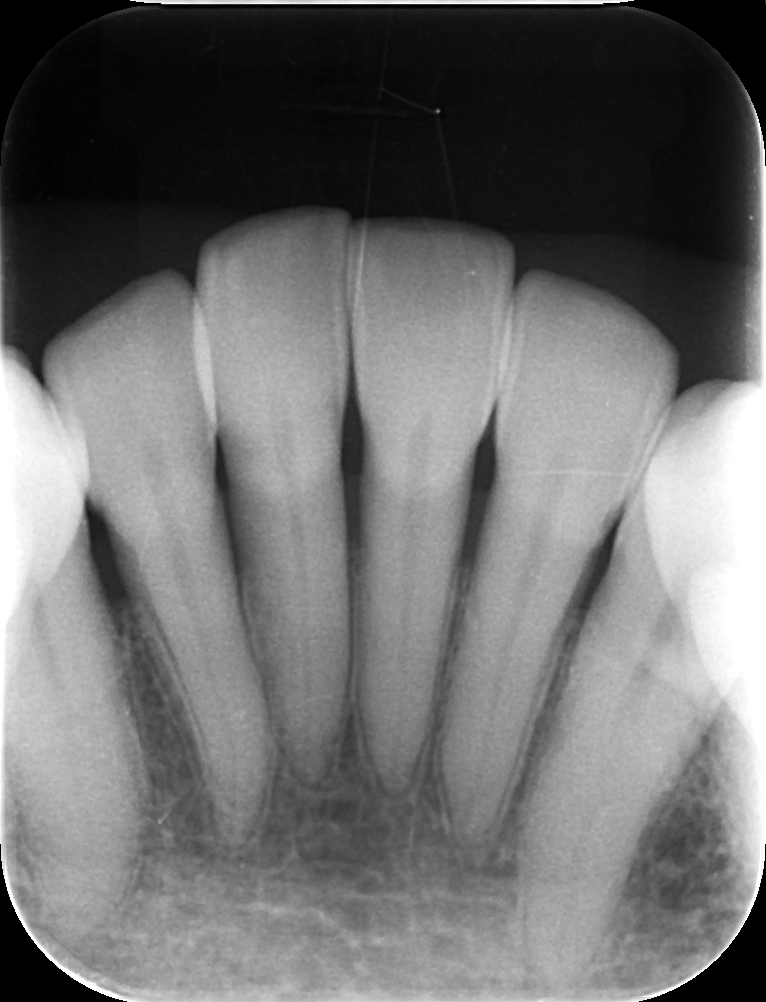

レントゲンではそれほどの異常は認められませんでした。